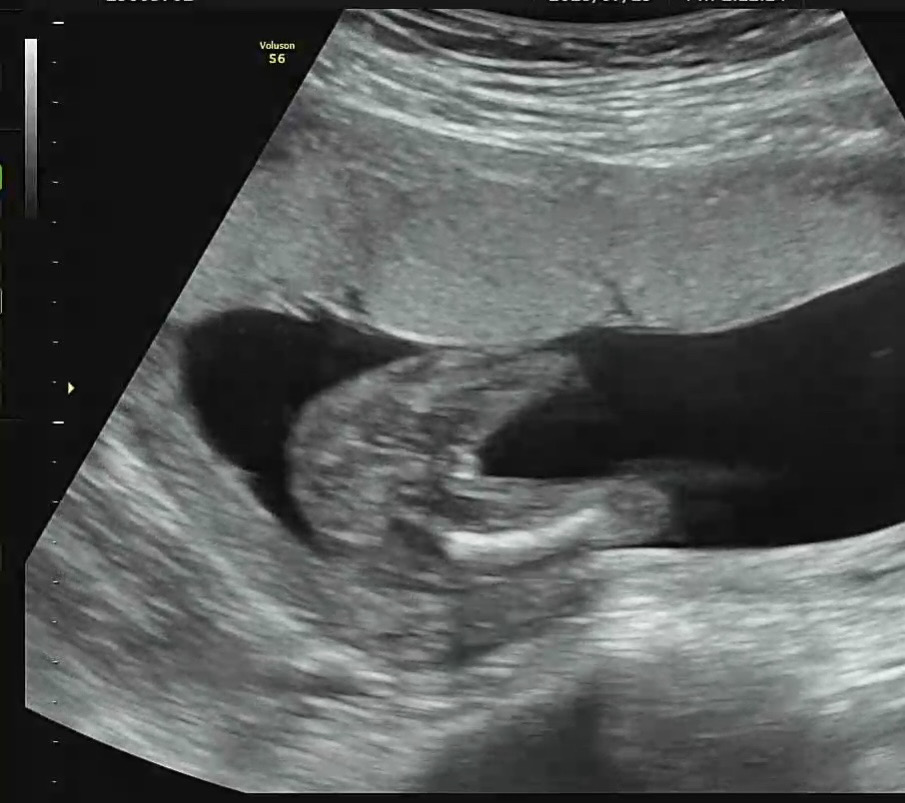

16주 성별 반전!!!!

병원에서 딸이라고 하셨는데 혹시 나중에 아들 반전 있을까요??????

딸에서 아들은 변하는확률이있대요! 반대로 아들에서 딸일확률이 거의없다하더라구요

딸은 20주까진 듀고봐야한다했어용ㅎㅎ 딸에서 아들반전은 많이보ㅑㅆ어요

네넹 저희병원이 보수적이긴한데 16주에 확률이 높다고만하시고 각도상 위치상 안보인걸수도 있어서 확답은 못한다고 하시더라구용..ㅎㅎ....

16주쯤 성별은 반전 잘 없어요! ㅎㅎ